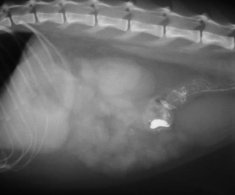

Thương hiệu Phòng Khám Thú – Y Chợ Lớn đã chính thức đi vào hoạt động từ năm 1998 đến nay đã trên 22 năm trong lĩnh vực chẩn đoán – điều trị bệnh trên thú nhỏ. Với đội ngũ các Thạc Sĩ, Bác Sĩ , Kỹ Thuật viên Thú Y dày dặn kinh nghiệm trong lĩnh vực thú y thú nhỏ, cùng với lòng nhiệt huyết, sự tận tâm và tình yêu thương động vật , chúng tôi đã và đang không ngừng tìm tòi học hỏi và mạnh dạn đầu tư nhiều trang thiết bị hiện đại nhằm đem lại hiệu quả hơn trong việc chẩn đoán – điều trị, với mong muốn mang đến những gì tốt nhất cho thú cưng của quý khách hàng. Chúng tôi triển khai hoạt động phòng khám với đa dạng dịch vụ như khám – chữa bệnh nội khoa, chẩn đoán hình ảnh bằng siêu âm, X-Quang, nội soi, điện tâm đồ, xét nghiệm sinh lý - sinh hóa máu, phẫu thuật, tiêm phòng, vật lý trị liệu, laser trị liệu, liệu pháp Oxygen , pet spa chăm sóc da & lông, pet shop, tư vấn chăm sóc & nuôi dưỡng thú cưng…